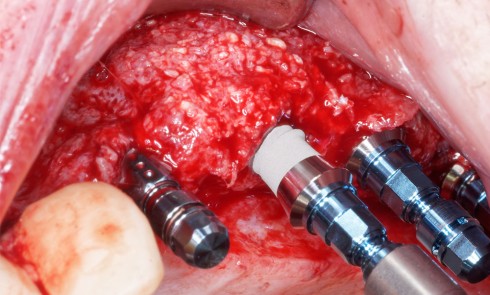

Au maxillaire, 3 implants Astra Tech Implant EV (Dentsply) sont posés en un temps chirurgical. Une empreinte pick-up sera réalisée après 4 mois de cicatrisation.

Une fois les transferts pick-up EV® transvissés, le porte-empreinte Tray, fenestré en regard des transferts, est chargé de matériau monophase Impregum™ Penta™ Soft (3M ESPE). Du matériau est déposé autour des transferts à l’aide d’une seringue. Après dévissage des transferts, ces derniers sont emportés dans l’empreinte et les analogues d’implants sont transvissés.

Une fois les transferts pick-up EV® transvissés, le porte-empreinte Tray, fenestré en regard des transferts, est chargé de matériau monophase Impregum™ Penta™ Soft (3M ESPE). Du matériau est déposé autour des transferts à l’aide d’une seringue. Après dévissage des transferts, ces derniers sont emportés dans l’empreinte et les analogues d’implants sont transvissés.

Une fois les transferts pick-up EV® transvissés, le porte-empreinte Tray, fenestré en regard des transferts, est chargé de matériau monophase Impregum™ Penta™ Soft (3M ESPE). Du matériau est déposé autour des transferts à l’aide d’une seringue. Après dévissage des transferts, ces derniers sont emportés dans l’empreinte et les analogues d’implants sont transvissés.

Une fois les transferts pick-up EV® transvissés, le porte-empreinte Tray, fenestré en regard des transferts, est chargé de matériau monophase Impregum™ Penta™ Soft (3M ESPE). Du matériau est déposé autour des transferts à l’aide d’une seringue. Après dévissage des transferts, ces derniers sont emportés dans l’empreinte et les analogues d’implants sont transvissés.

Une fois les transferts pick-up EV® transvissés, le porte-empreinte Tray, fenestré en regard des transferts, est chargé de matériau monophase Impregum™ Penta™ Soft (3M ESPE). Du matériau est déposé autour des transferts à l’aide d’une seringue. Après dévissage des transferts, ces derniers sont emportés dans l’empreinte et les analogues d’implants sont transvissés.